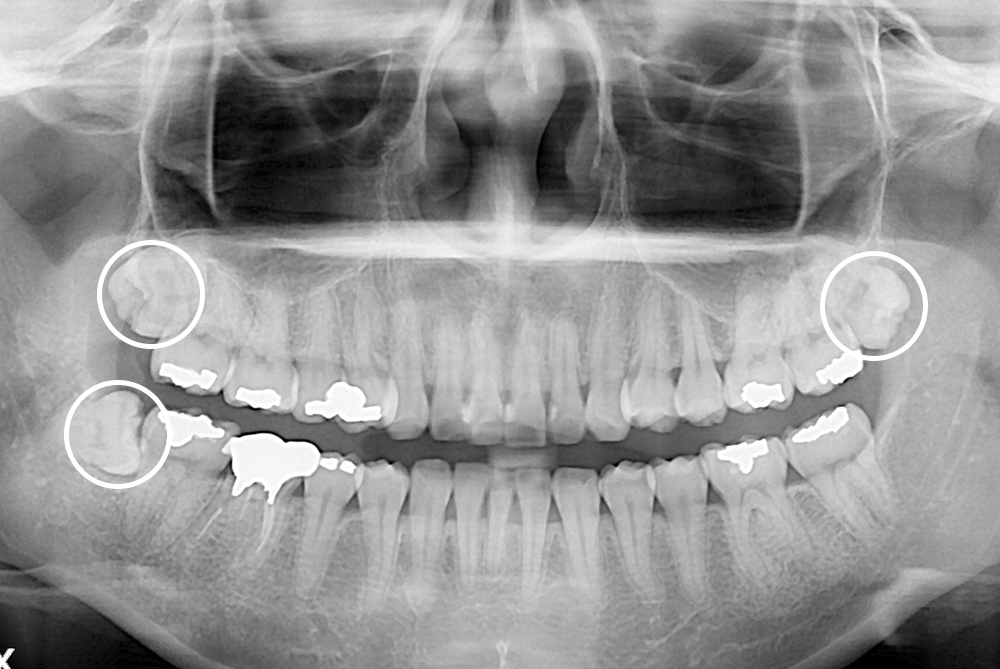

[사랑니] 매복 사랑니 발치

치료전 : 2020-01-11

세종치과는 구강악안면외과학 박사이신 원장님이 발치하는 치과입니다.